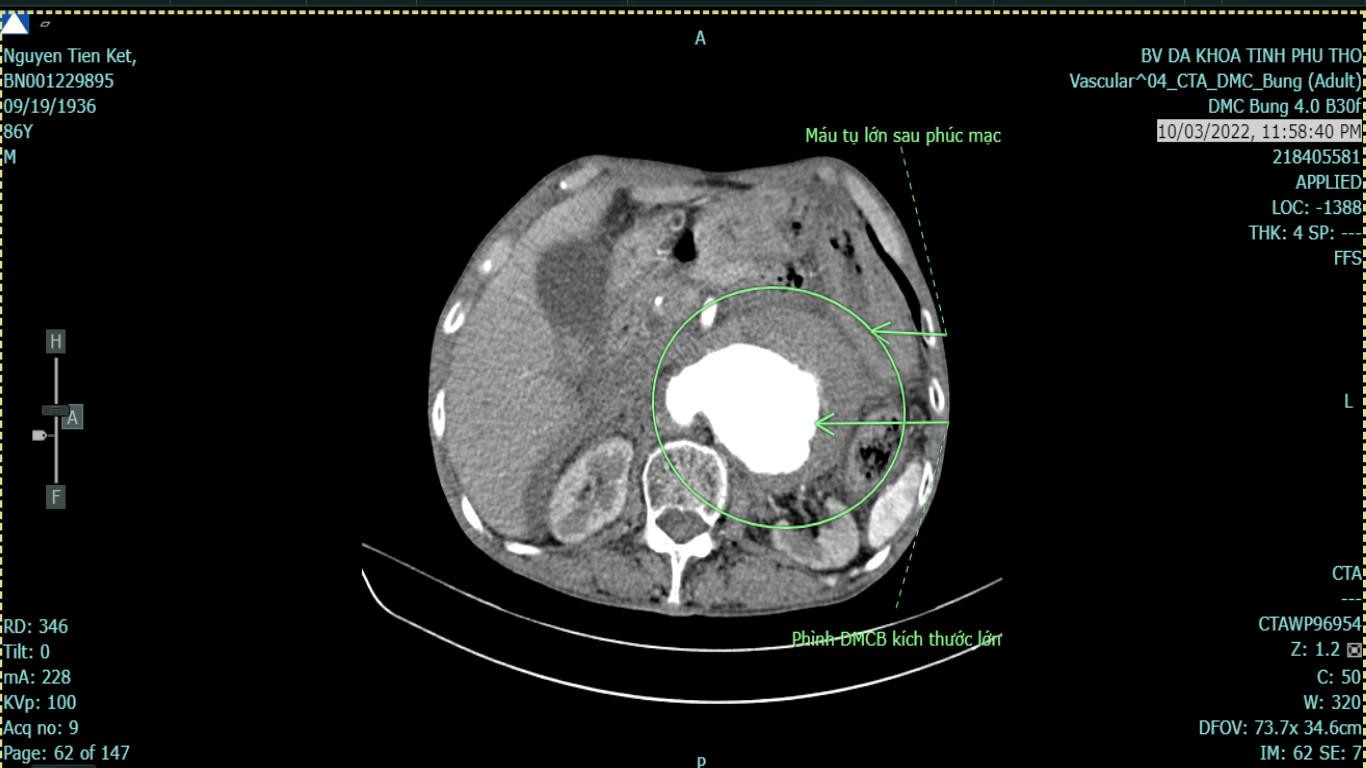

Tại Bệnh viện Đa khoa tỉnh Phú Thọ, người bệnh được hồi sức và chụp cắt lớp vi tính cho thấy người bệnh bị phình động mạch chủ bụng kích thước lớn, vỡ sau phúc mạc.

| Hình ảnh máu tụ lớn sau phúc mạc của người bệnh. Ảnh: Bệnh viện cung cấp |